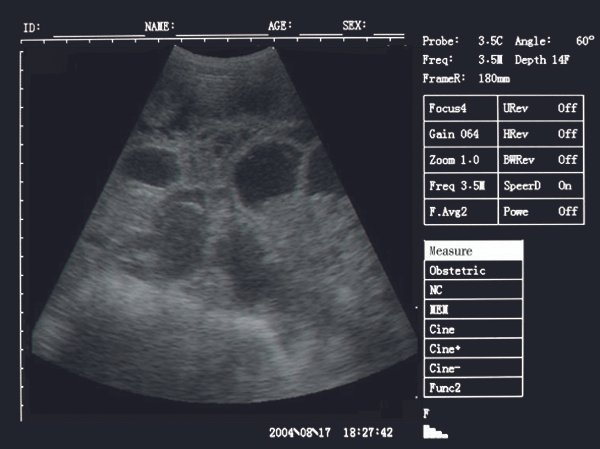

Firstly, just like in humans, we can use it to look at the uterus – for example, at the puppies and kittens living there. SIFULTRAS-4.2 allows you to see whether the animal is pregnant at a very early stage, and assess how healthy the babies are. Even more importantly, a Waterproof Portable Veterinary Ultrasound Scanner can examine the uterus in a sick animal to determine whether or not she has a pyo (a potentially fatal womb infection).

Secondly, a Waterproof portable machine can examine other abdominal organs – the intestines, the kidneys, the bladder, the spleen, and the liver. This way, the VET can check for tumors, twists, and other injuries, without having to open up the patient in surgery. The doctor can use a Waterproof Portable Veterinary ultrasound machine to see if there is free blood or fluid inside the abdomen that might indicate internal bleeding; or guide a biopsy needle to a suspicious lump, without needing surgery.

Thirdly, you can examine tendons and ligaments. This is useful in dogs and cats.

Finally, a Waterproof Portable Veterinary ultrasound machine can look at the beating heart of a dog or cat. The Vet can measure the amount of blood backing up in the atria (a marker of heart failure), see how thickened or thin the walls of the heart are, measure the speed of blood passing through a narrowed vessel or even see blood leaking through a damaged valve. This has genuinely revolutionized cardiology for dogs and cats.

Scan results :